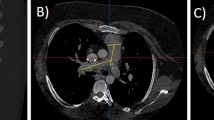

All measurements were performed on a cardiovascular imaging workstation (Circle CVI42; Circle Cardiovascular Imaging Inc. Alberta, Canada) after studies were anonymized. All images were visualized in axial, sagittal, and coronal planes with a window (600–900) and a level (250–350) settings. Double-oblique planes were obtained using multiplanar reformatting to measure MPA midway between the pulmonary valve and PA bifurcation. The proximal branch PAs were measured immediately after the PA bifurcation, all measures were made en face [20, 29]. Maximum, minimum, and mean diameters and cross-sectional area for MPA and branch PAs by planimetry were measured (Fig. 1). The measurements were categorized as either systolic or diastolic as described above.